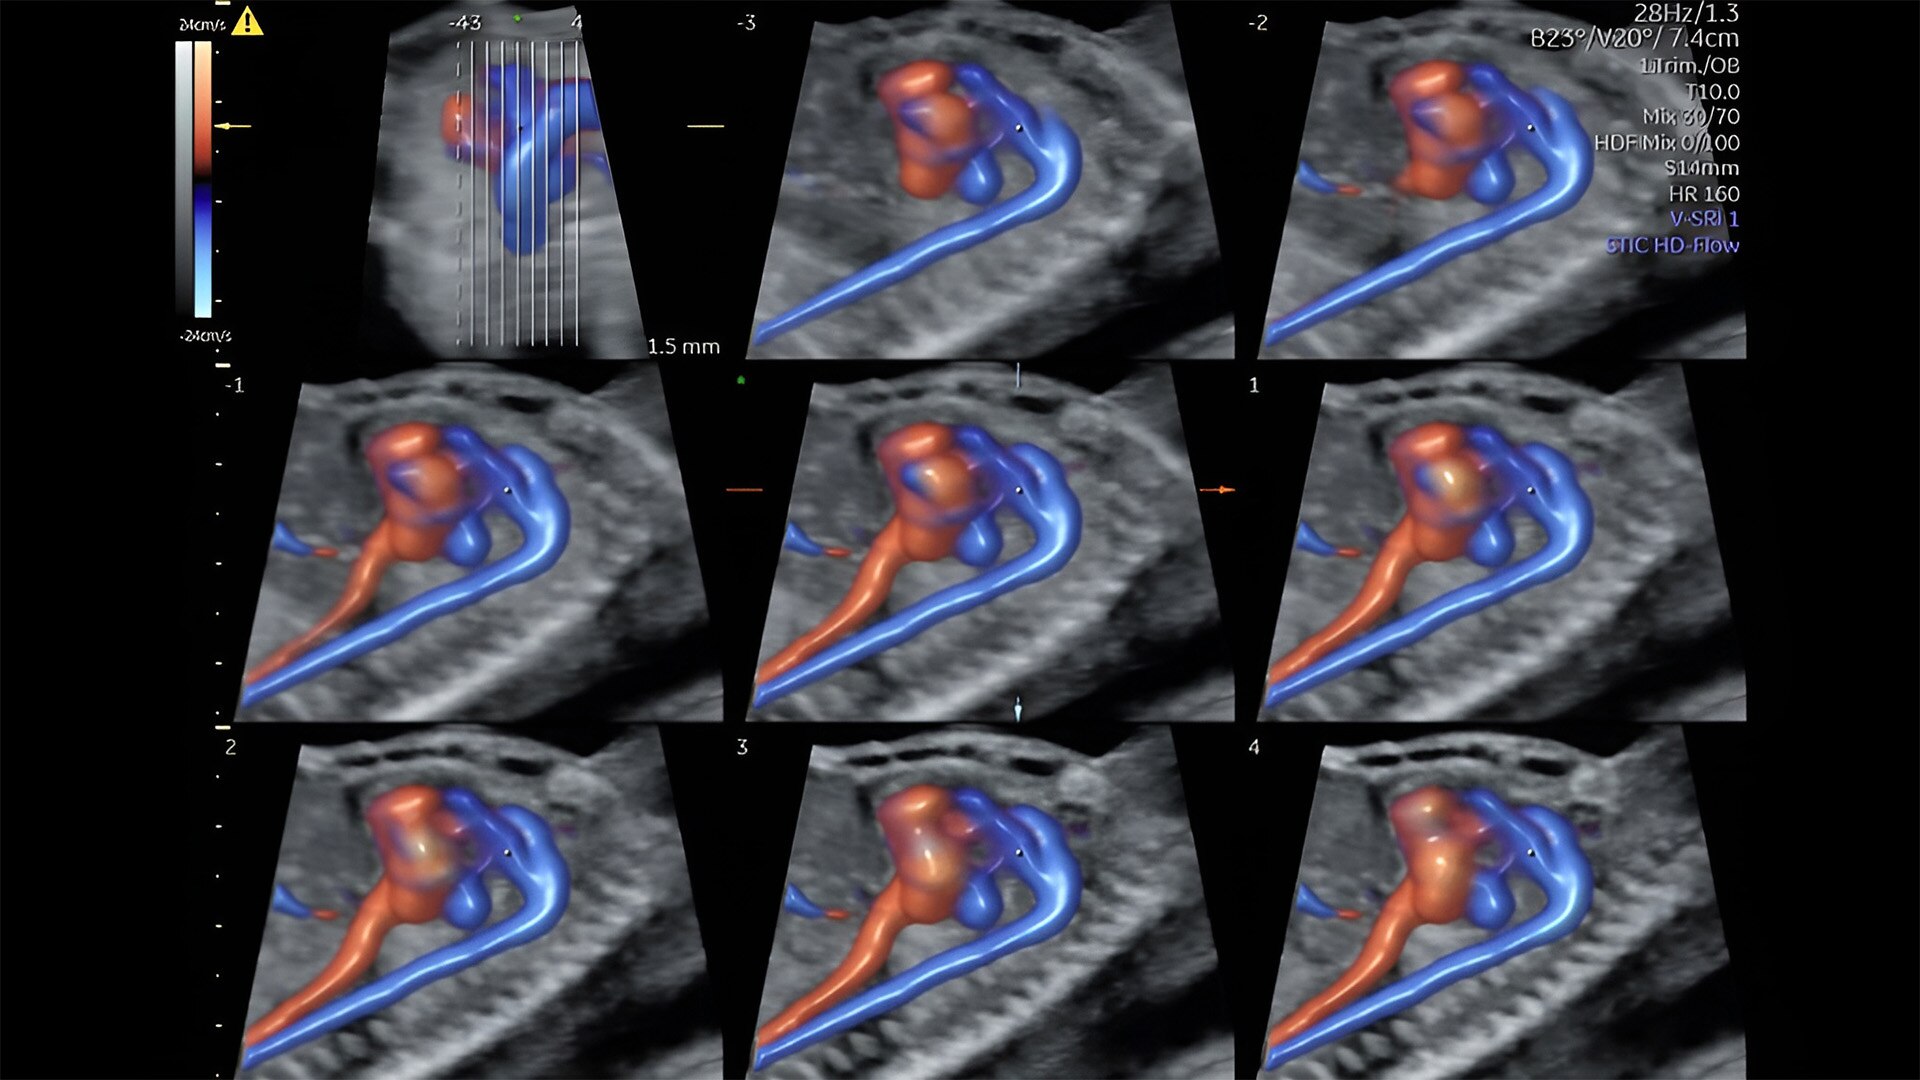

Fetal heart assessment

Detect, diagnose, and monitor with confidence using Radiant and fetalHQ

Fetal heart evaluation

Get to the heart of the matter

Identifying fetal cardiac abnormalities earlier means you can intervene sooner, plan for delivery, and potentially improve outcomes. The Voluson Expert 22 provides a full solution of progressive tools, to help distinguish the tiniest structures with stunning clarity to provide patient answers faster.